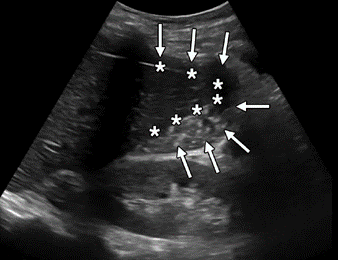

The amount of free fluid detected at a specific point in time depends on the rate of accumulation, location, and the patient’s position [9]. Free fluid gravitates to the most dependent area, which is the right upper quadrant (RUQ) in a supine patient [16]. Within the RUQ, the hepatorenal recess (also known as Morison pouch) is a common area of interest; however, the caudal tip of the liver is where fluid tends to collect first. In the left upper quadrant, attention should be directed to the perisplenic area, particularly in the subdiaphragmatic space. In the pelvis, fluid tends to collect posterior to the uterus, known as the pouch of Douglas, in females and in the rectovesicular space or lateral to the bladder in males [17] (Fig. 2).